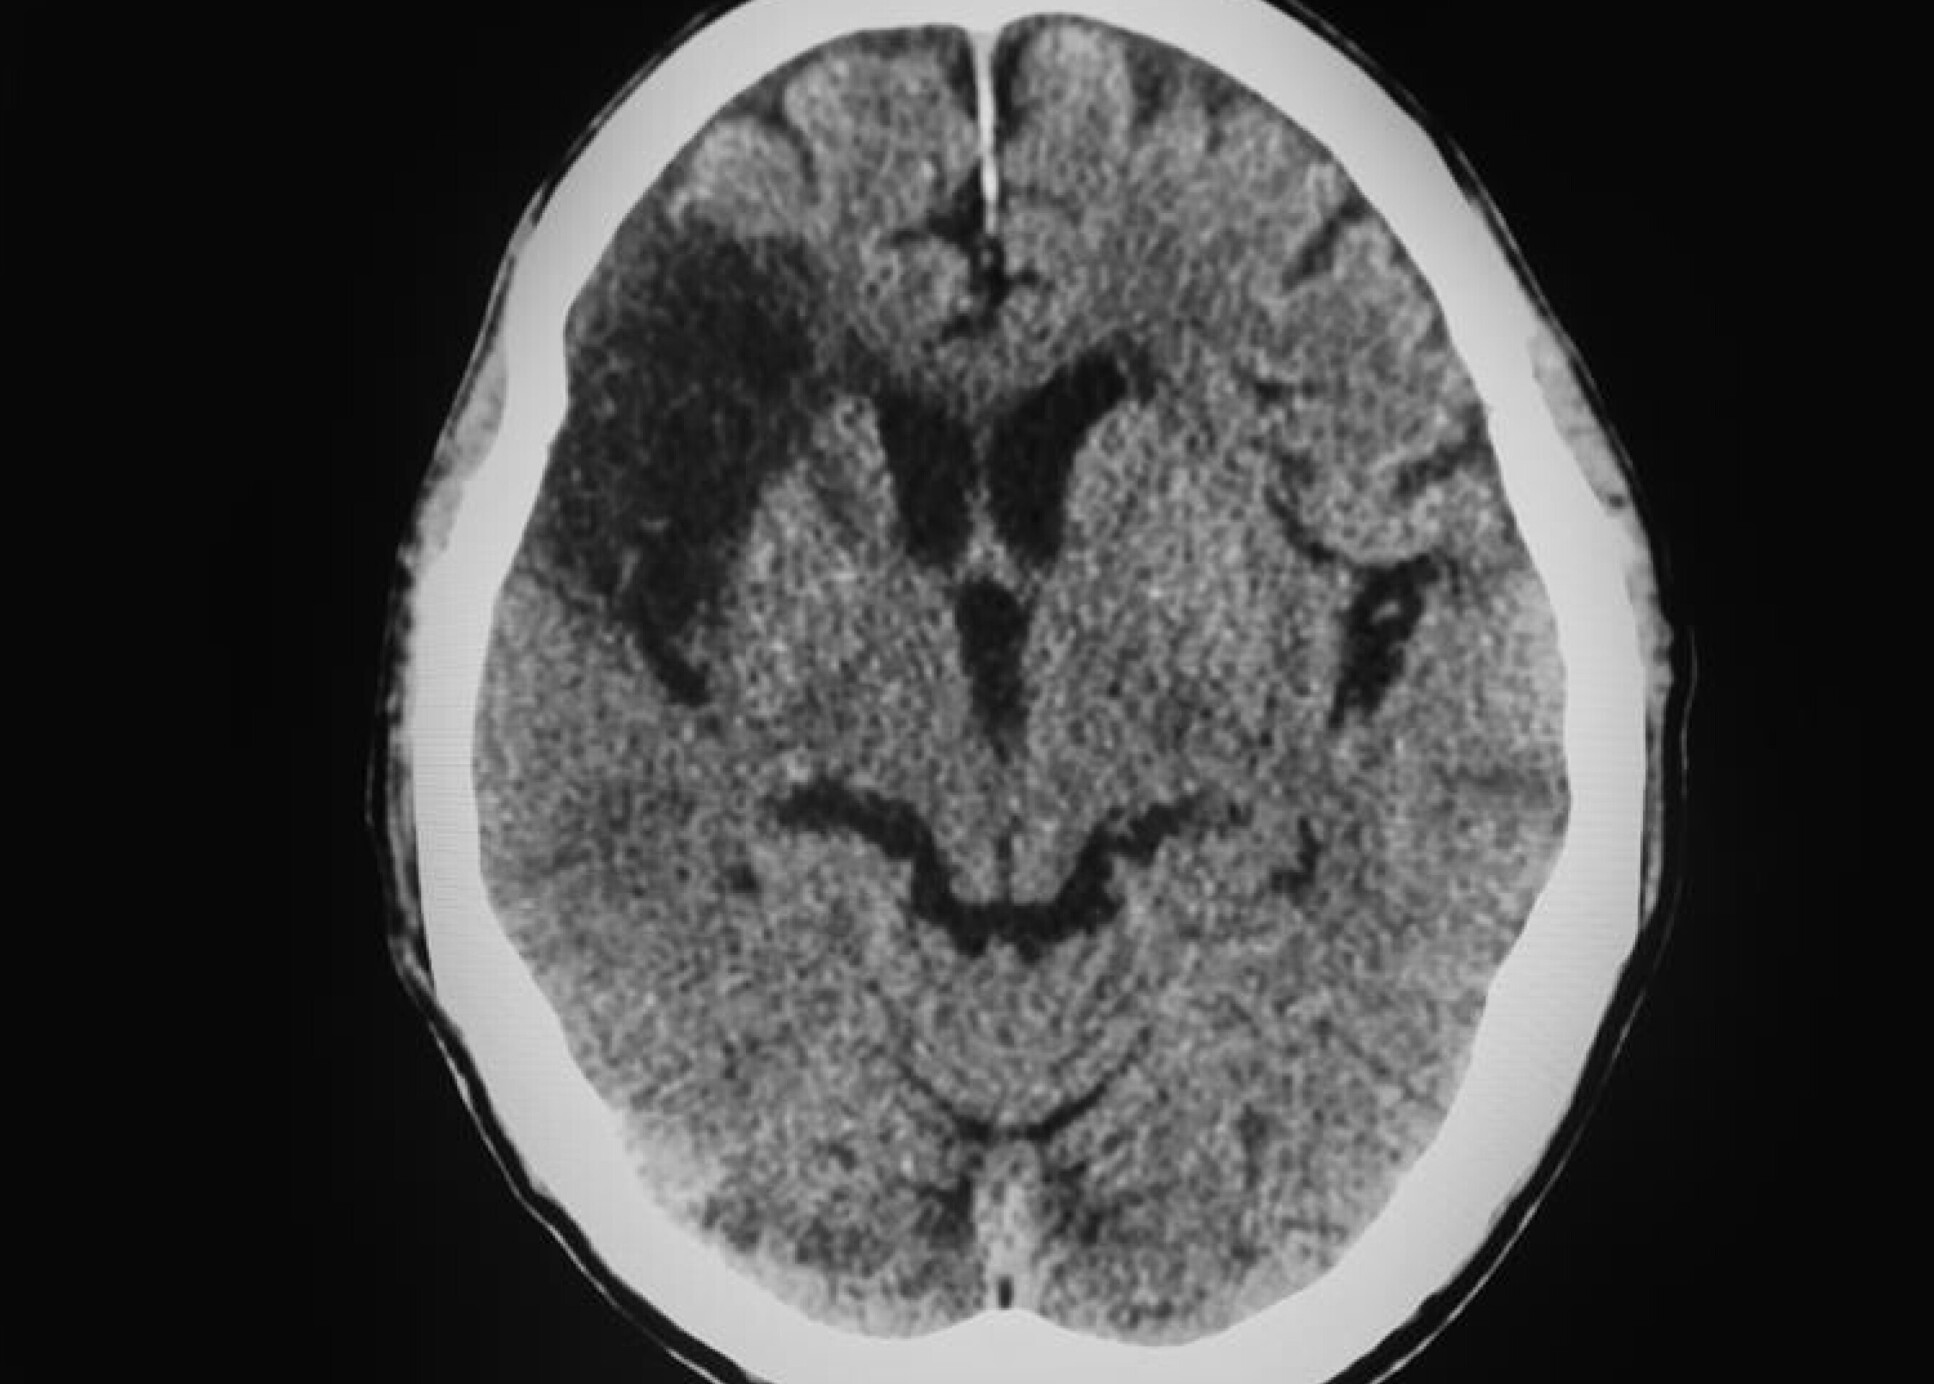

New AI stroke brain scan readings are twice as accurate as current method

A medical CT scan of the brainImperial researchers, in collaboration with the Universities of Munich and Edinburgh, have developed AI software that analyses brain scans to determine the onset time of strokes. Identifying the precise start time is critical as treatments vary in the first few hours post-stroke.

This information enables doctors to make decisions that maximises the patient’s chance of reversal, ensuring no secondary damage is caused.

The model was trained on hundreds of medical scans where stroke time was known. By also extracting additional medical data from the scan, such as texture, the AI can identify the start time of strokes 50% more successfully than the standard visual technique of doctors, ultimately enabling faster and more accurate treatment of patients in emergencies.